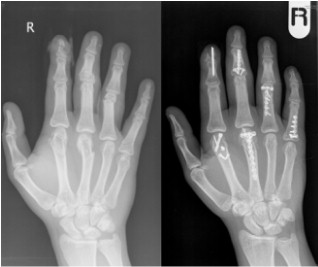

Congenital Hand Problems

Congenital Hand Problems are a group of conditions wherein the children’s hands exhibit differences in form in terms of shape, number or length of the digits. Examples include syndactyly and thumb duplication. A thorough examination is typically conducted to ensure that other organ systems are not compromised, as observed in a small proportion of these cases. Diagnostic measures, including X-rays of the hands, are used. Corrective procedures are planned following detailed consultation with the child’s parents to understand their expectations.

Corrective surgery for thumb duplication.